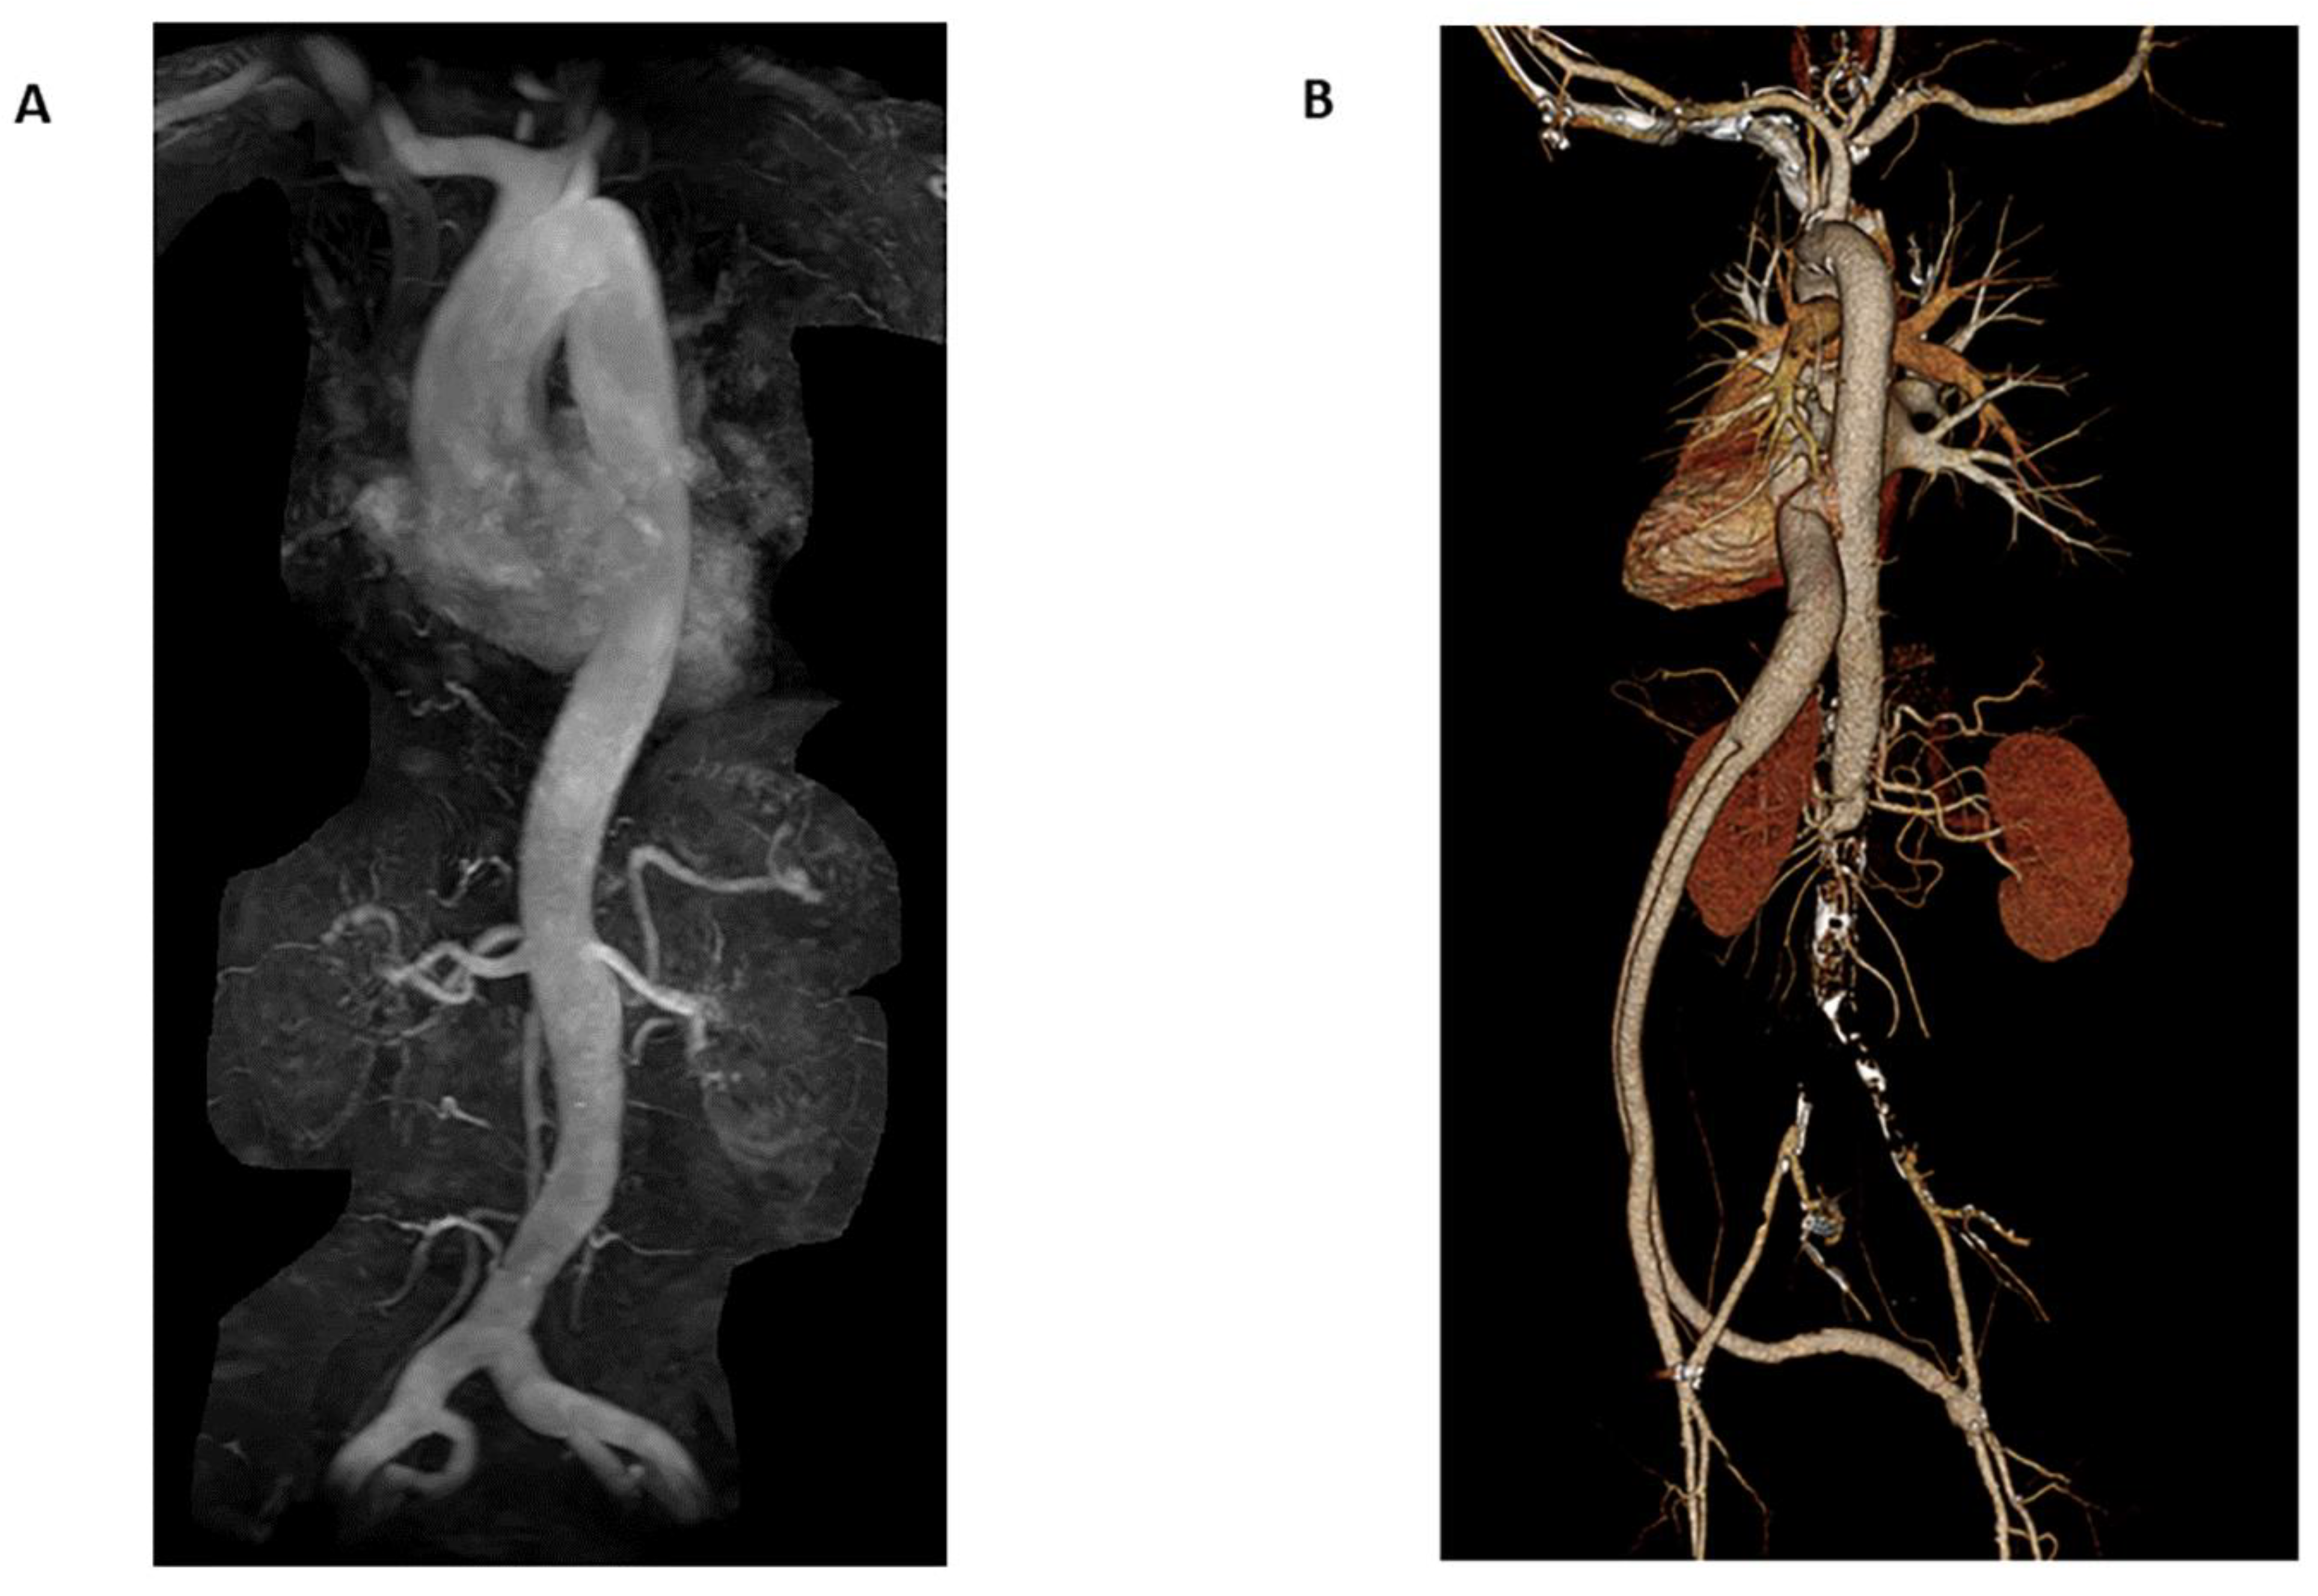

3.2.1. Magnetic Resonance Angiography

3.2.2. Open and Larger Bore MRI